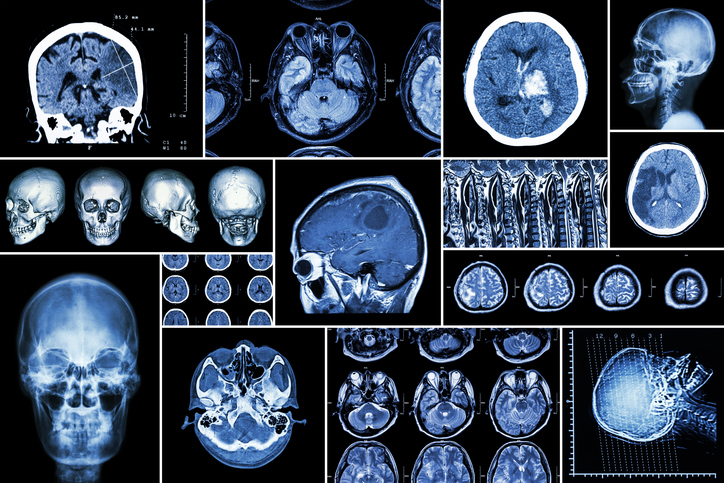

Les glioblastomes multiformes (GBM) sont une forme courante de cancer du cerveau qui touche les astrocytes (des cellules du système nerveux central). Les tumeurs qui se développent sont particulièrement agressives, tuant environ 95 % des patients dans les cinq ans. Ce cancer touche environ 3 personnes sur 100 000 et frappe surtout les plus de 60 ans. Mais tandis que de nombreux chercheurs réfléchissent à de nouvelles manières de traiter les gliomes, la détection précoce de ce cancer est le plus souvent accidentelle et non intentionnelle. Cette nouvelle étude pourrait inverser la tendance en stimulant les chances d’un diagnostic beaucoup plus précoce.

Cette étude récente ne s’arrêtait pas au balayage du génome. Il avait également analysé plus de 30 000 personnes incluses dans un certain nombre d’études précédentes sur les cancers GBM et non GBM, constituant ainsi la plus grande étude faite sur le cancer du cerveau. En comparant 12 496 cas de gliome avec 18 190 personnes qui n’étaient pas atteintes par le cancer, les chercheurs ont identifié une douzaine de nouvelles mutations qui pouvaient conduire à l’apparition d’une tumeur. Ainsi des causes génétiques pourront nécessiter des approches différentes de traitement.